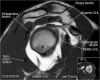

어깨 관절의 MRI 단면영상

- Sagittal section

1) T1WI : Rotator cuff muscle size, fat infiltration, Biceps tendinosis

2) T2WI : Rotator cuff insertion, edema, Rotator cuff partial or full thickness tear, Bursa fluid collection, Acromial type ,Glenoid fossa, Superior, middle, inferior GHL

근육 안에 tendon이 들어있다

원외부에서 SST와 IST가 겹침